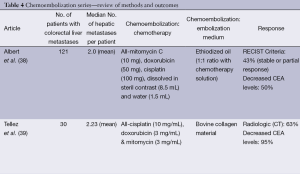

Hepatic artery chemoembolization is appropriate for patients with liver dominant metastatic disease, ECOG performance status of 0-2, and preserved liver function with serum bilirubin of less than 2 mg/dL. Ideally the portal circulation is preserved and tumor volume is less than 50%. Standard chemoembolization protocols include a variety of agents but often include mitomycin, doxorubicin and cisplatin emulsified in ethiodized oil (38). Treatment is performed in a lobar distribution starting with the more affected lobe and followed by treatment of the contralateral lobe in 15 to 30 days. Bilobar treatment is considered one cycle. Response is assessed with CT or MR imaging at 30-90 days and treatment cycles are repeated as necessary for disease progression. Most often, chemoembolization is considered after failure of first and second line chemotherapy. In a report by Albert et al., using the previously mentioned standard method of chemoembolization with mitomycin C, doxorubicin, and cisplatin mixed with ethiodized oil, the authors reported partial response, stable disease, and disease progression in 2%, 41%, and 57% of patients, respectively. Median time to liver progression was 5 months and overall disease progression was 3 months. Median survival following the first chemoembolization was 9 months (38). These results are similar to other series reporting median survivals of 8-14 months from the time of first chemoembolization (39-41). Complications of chemoembolization are common but most often minor, including the anticipated post embolization syndrome of fever, nausea, vomiting and abdominal pain, which are usually easily controlled and of limited duration. More serious complications including liver failure, renal failure, liver abscess, cholecystitis, myocardial infarction and pulmonary embolus have also been reported

In most reports, prior to DEBIRI chemoembolization, patients had undergone previous chemotherapy and failed at least one line of chemotherapy, with some having failed two or three regimens of chemotherapy. In general, patients tolerate DEBIRI well with the most common adverse event being the post-embolization syndrome. Abdominal pain, occasionally severe, is reported in 40-63% of patients. Hypertension is also frequently reported but is most often transient and related to pain. Aliberti reported results in 82 patients who failed initial lines of chemotherapy with response to DEBIRI of 78% at three months, progression free survival of 8 months and median survival of 25 months (42). These results are similar to those reported by Martin with response at 6 and 12 months of 66% and 75%, and progression free and overall survivals of 11 and 19 months, respectively (43). Other reports and meta-analyses report response to treatment in 18-78% of patients with median survival rates of 15-25 months (44). Patients failing only first line chemotherapy exhibit better overall response and survival compared to patients having failed multiple lines of chemotherapy. In a randomized trial comparing DEBIRI to 5-fluorouracil (5-FU)/leucovorin/irinotecan in patients failing first lines of chemotherapy, time to progression and overall survival favored DEBIRI at 7 and 22 versus 4 and 16 months, respectively (44). Toxicity including neutropenia, diarrhea, and mucositis were less frequent in the DEBIRI group (44). Both standard chemoembolization and DEBIRI have been reported to downstage up to 20% of patients to surgical resectability (45) (Table 4).